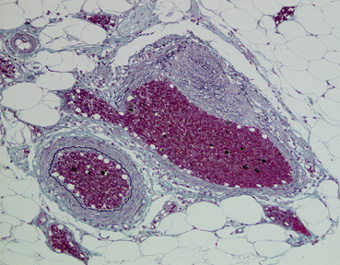

漿膜下層の静脈壁の筋層が不均一に肥厚している.(EM,×10) |